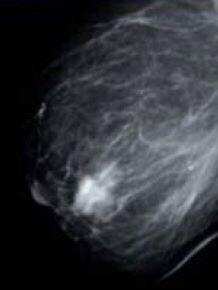

Se realiza mamografÃa de la mama derecha en la que aparece lo que se muestra en la imagen. ¿Cuál serÃa la conducta terapéutica más apropiada?:

1. La mamografÃa es normal. Continuaremos con el screening normal, siendo el siguiente control a los dos años.

3. Complementar el estudio con ecografÃa y, si ésta es normal, control dentro de un año.

4. Punción de la lesión en consulta, con estudio citológico del resultado de la misma.

5. Biopsia diferida, previo marcaje con arpón.